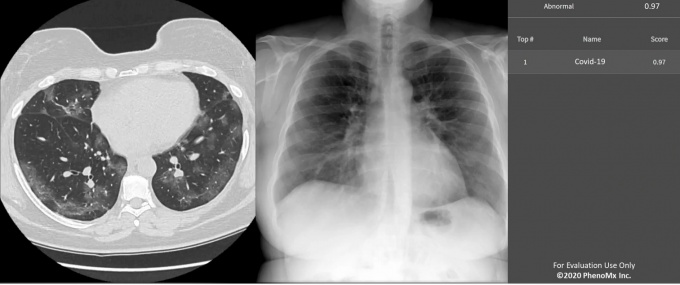

[사진설명 : 인공지능이 폐CT 및 X-RAY 영상을 통해 신종 코로나바이러스 침범 수치를 제시한 결과]

코로나19 AI 진단 지원 서비스 ‘피노체스트AI'는 코로나19 확진자의 폐 CT와 X-ray 영상데이터 등을 기반으로 한 딥러닝 알고리즘을 통해 코로나19 확진 여부를 수 초 안에 신속하게 구별하는 AI 의료영상 분석기술이다.

Phenochest-AI는 바이러스 진단 키트 상 양성으로 판정된 환자들을 대상으로 촬영한 Xray와 CT상 바이러스 침범 지수를 수 초 내 자동으로 제시한다.